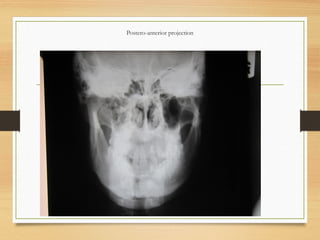

 Extraoral views

 Postero-anterior projection shows mediolateral

displacement of fracture of the body, angle, ramus

or condylar regions

Postero-anterior projection